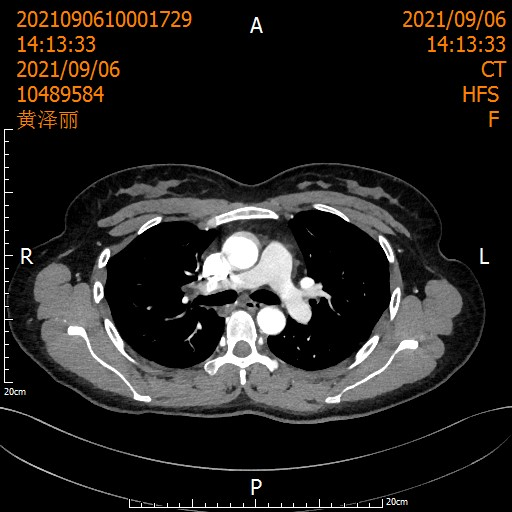

5年前,一位40岁的母亲因"咳血三月"到胸心外科就诊。CT结果显示:右上肺门区肿块,支气管粘液栓。活检确诊为非小细胞肺癌(T3NxM0)。

患者术前影像